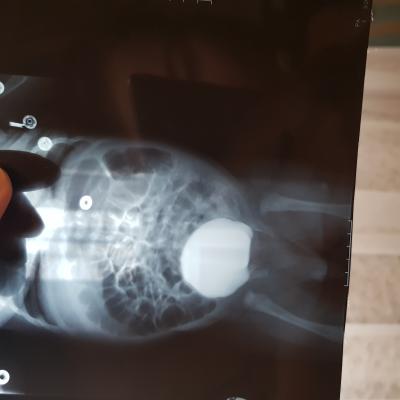

Добрый день! Еще внутриутробно у ребенка обнаружили расширение лоханок.Провели обследование в 1.5 месяца.Поставили диагноз болезнь Ормонда.И назначили консервативное лечение.В 2ух мочеточниках по несколько наростов.рефлюкса не было.Скажиье, возмлжнл что ребенок поосто перерастет?

Болезнь Ормонда (ретроперитонеальный фиброз, забрюшинный фиброз) – хроническое воспаление жировой клетчатки забрюшинного пространства, которое постепенно приводит к компрессии и нарушению проходимости трубчатых структур данного анатомического участка. Чаще всего, в качестве этих тубулярных структур выступают мочеточники.

У меня есть сомнения, что причиной гидронефроза в Вашем случае явилось именно это состояние.